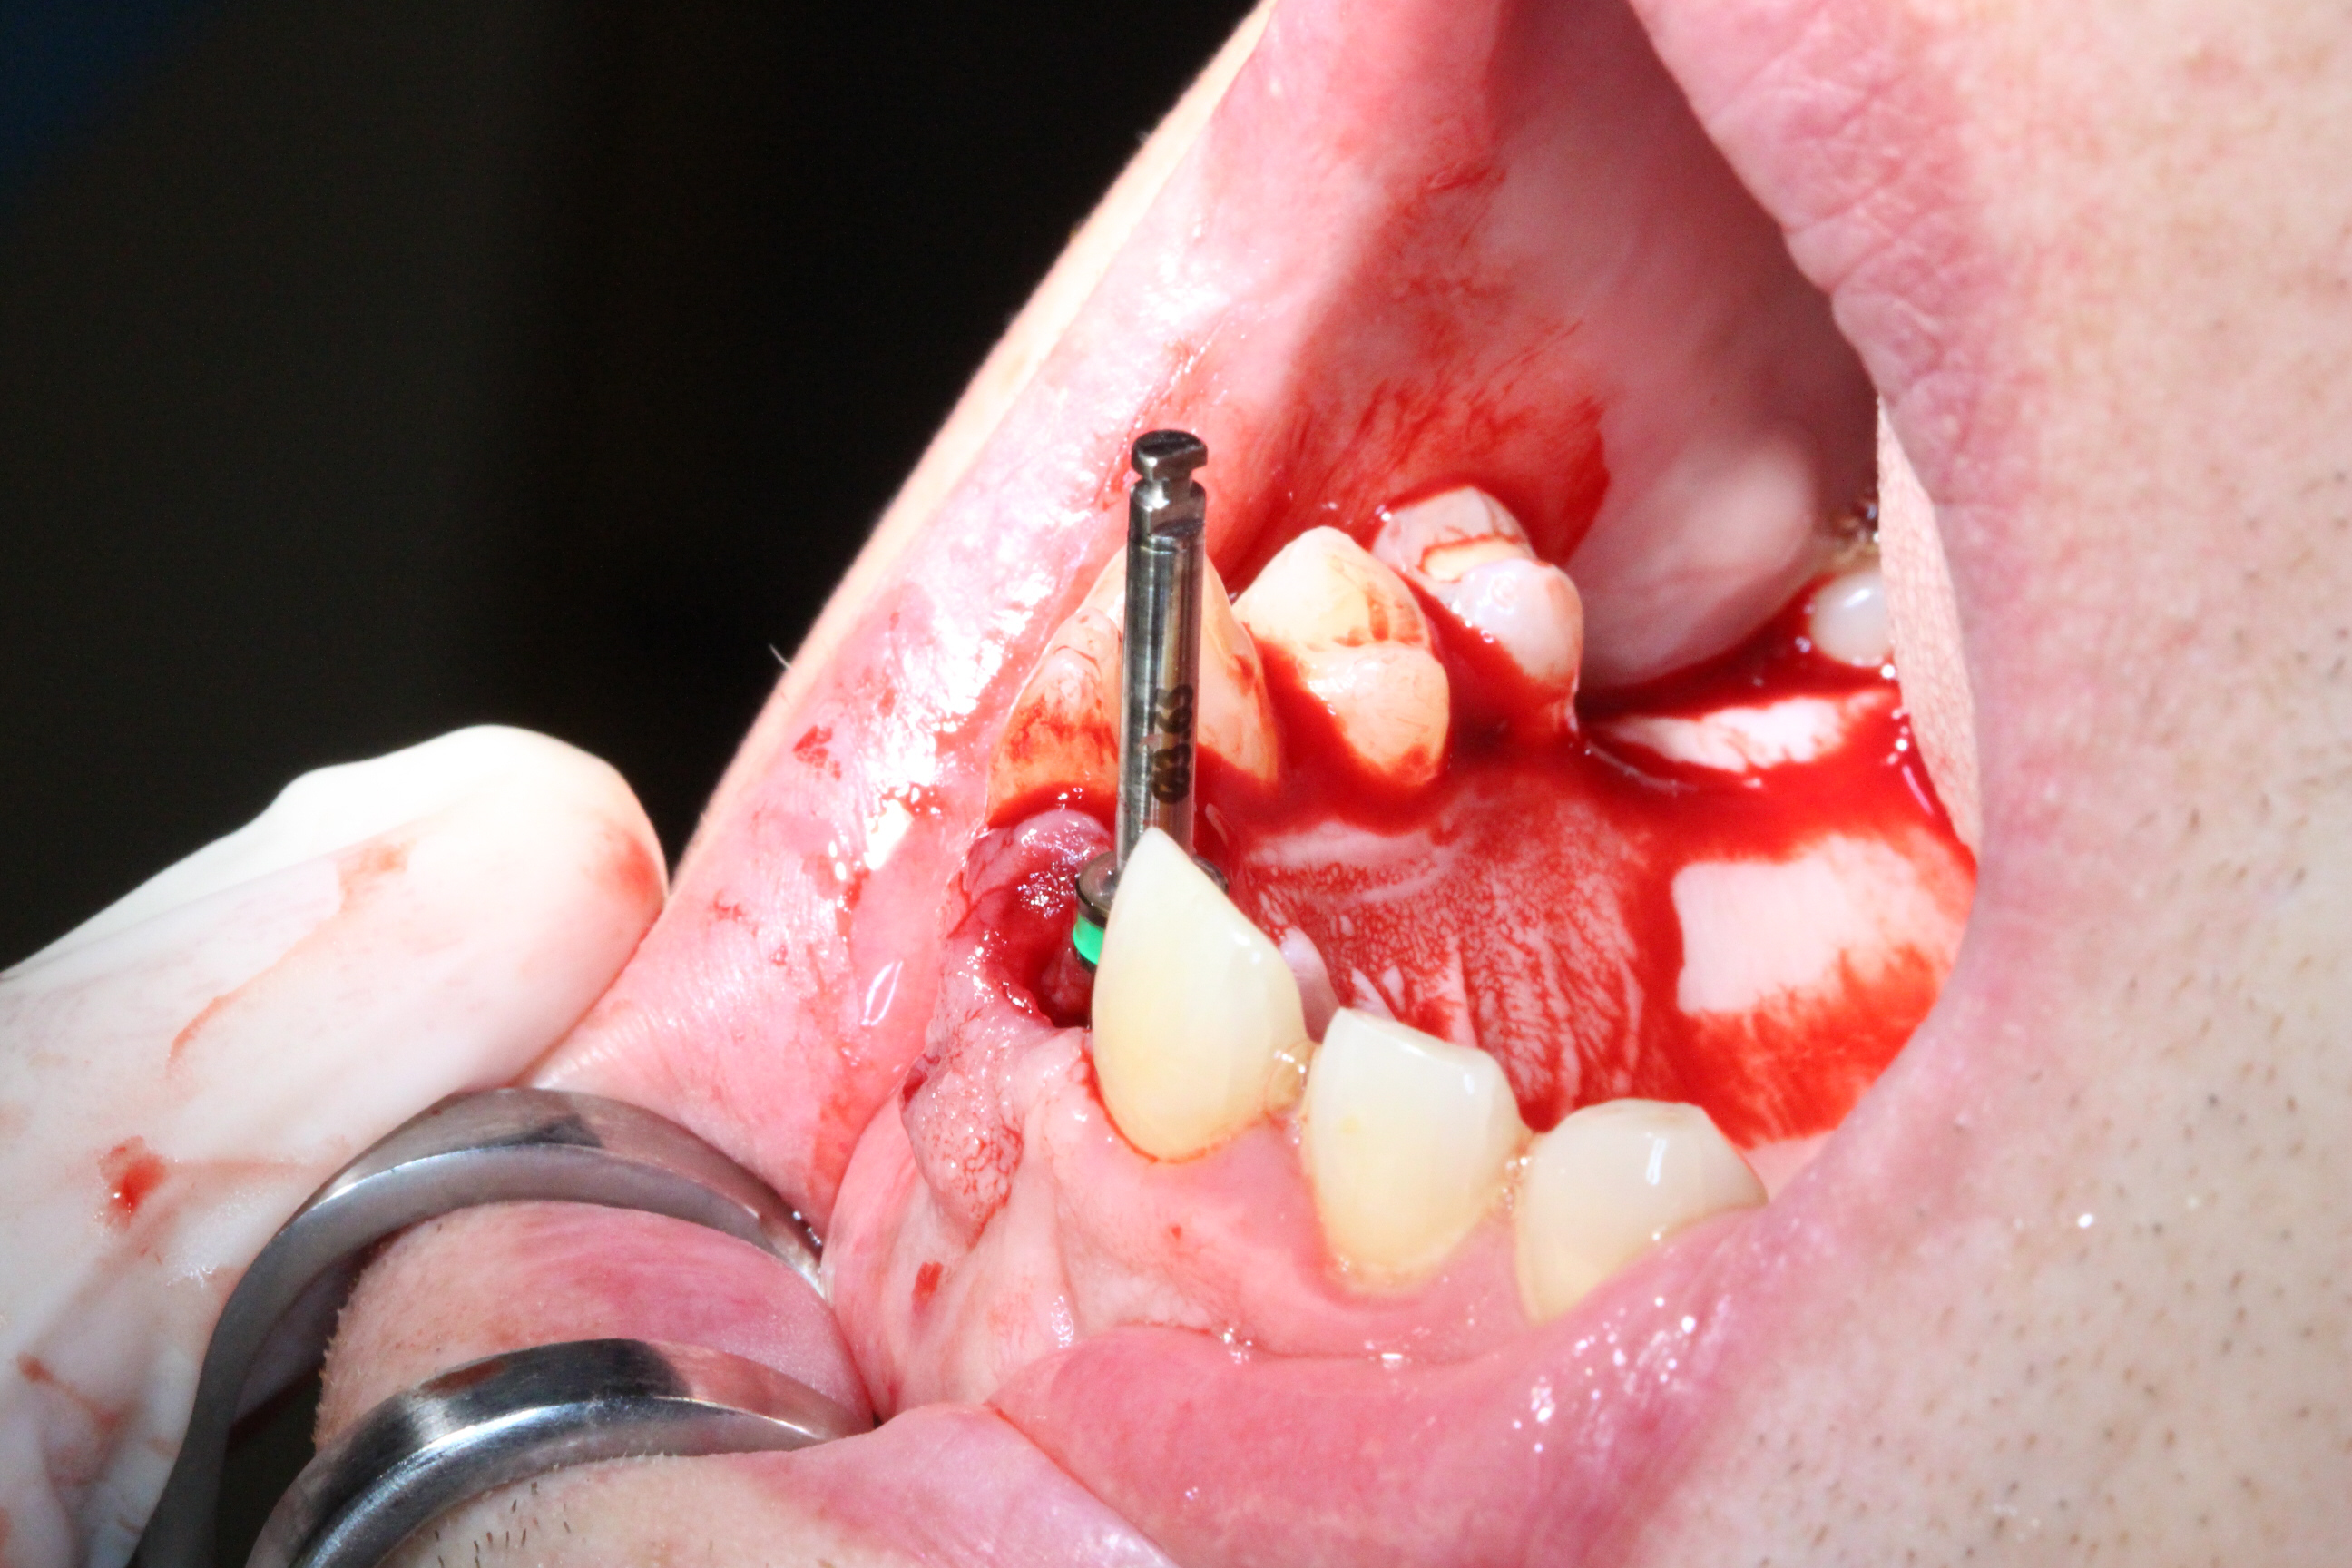

The surgical procedure was performed by oral surgeon Dr. Amir Ashourioun.

An atraumatic extraction of tooth 21 was performed without flap elevation in order topreserve the soft tissue architecture.

The DICOMLAB surgical guide was positioned, and the implant was placed according to the digital plan.

Implant placed: DSI Conical Implant – 4.3 × 13 mm.

Primary stability achieved: 45 Ncm insertion torque.

Achieving this level of stability and ideal prosthetic positioning would have been extremely difficult without guided surgery due to the severe buccal bone deficiency.